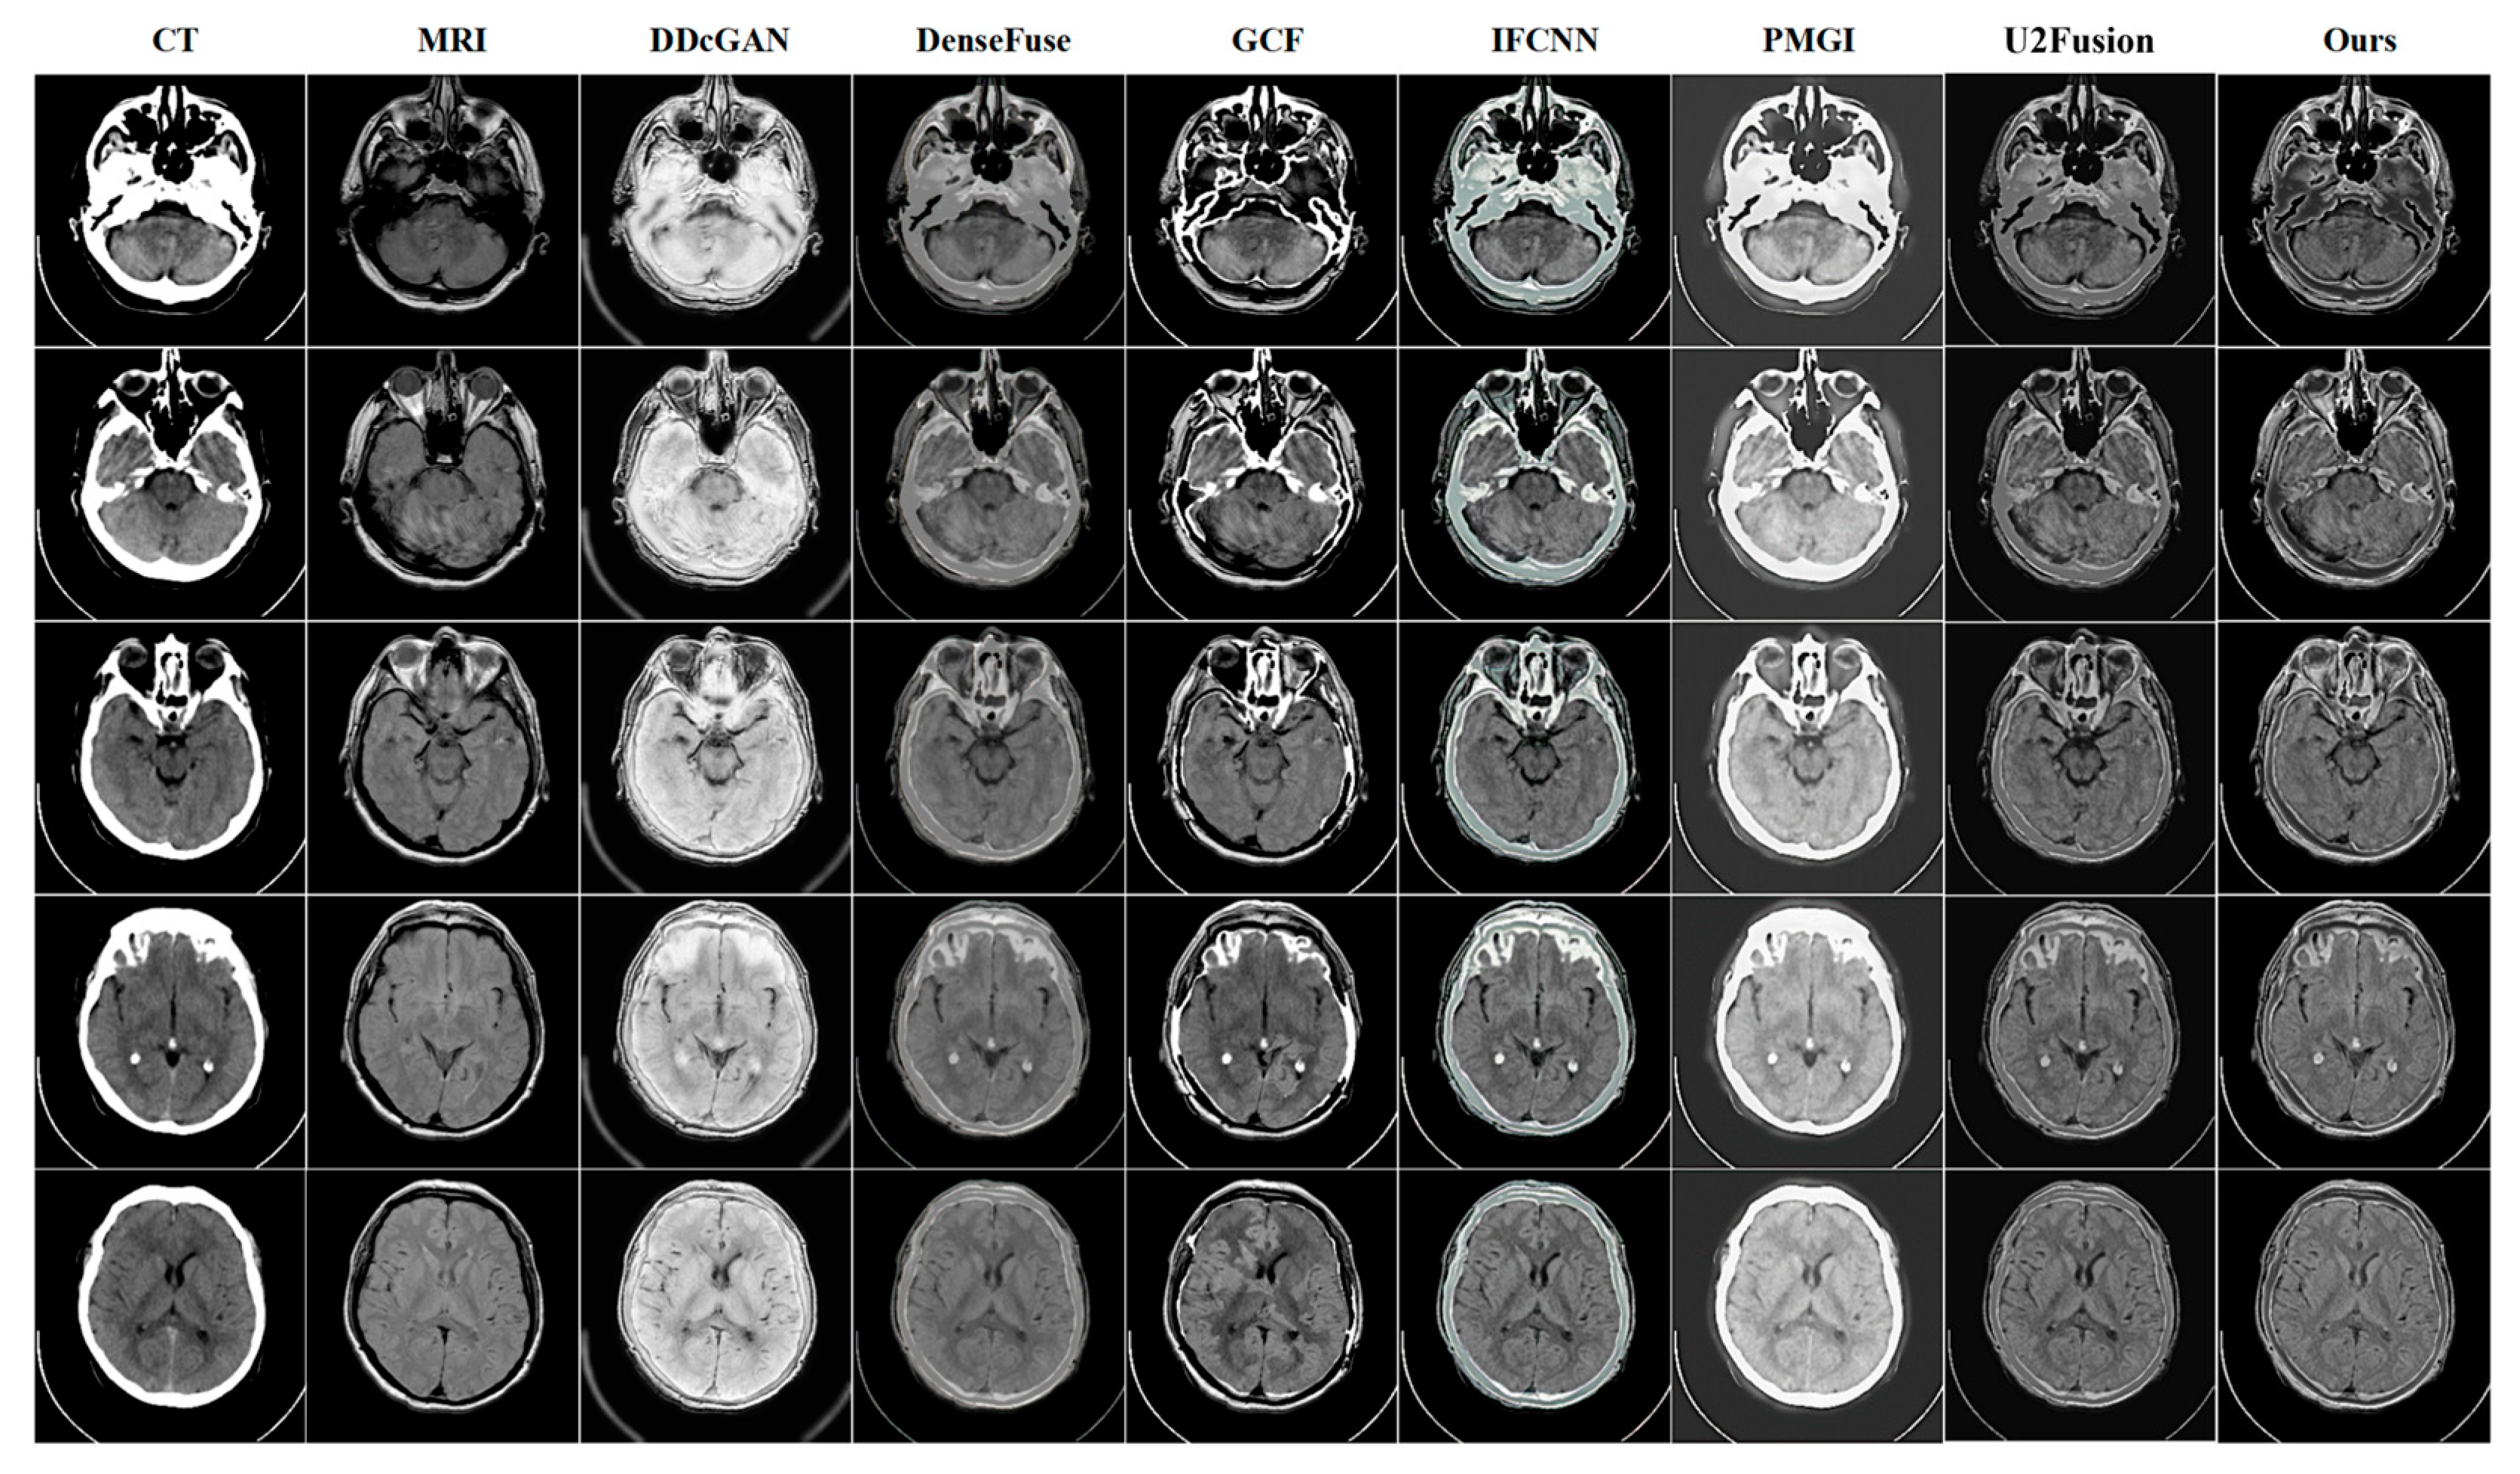

4.3. Quantitative and Qualitative Comparison Results

CT-MRI | DDcGAN | DenseFuse | GCF | IFCNN | PMGI | U2Fusion | Ours |

---|---|---|---|---|---|---|---|

AG↑ | 9.0754 | 5.6772 | 9.1627 | 7.7264 | 7.895 | 6.8957 | 10.1333 |

EI↑ | 91.0206 | 57.5941 | 97.2749 | 81.7838 | 79.8071 | 70.5399 | 99.7997 |

Qabf↑ | 0.3563 | 0.3393 | 0.5682 | 0.5122 | 0.508 | 0.4102 | 0.5402 |

Qcv↓ | 4974.886 | 2599.490 | 4902.781 | 1922.205 | 1592.081 | 2610.5305 | 3376.064 |

CT-MRI | SwinFusion | 9.2796 | 94.1302 | 0.6059 | 2100.6508 |

BPDGAN | 10.1333 | 99.7997 | 0.5402 | 3376.064 | |